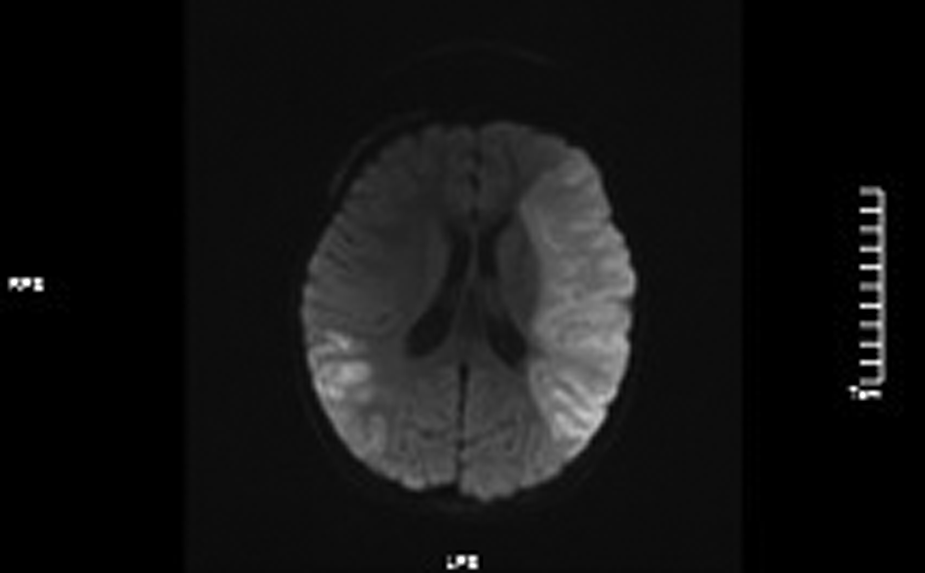

Figure 6

DWI images showed high signals in the left frontotem poral lobe and the right temporal.